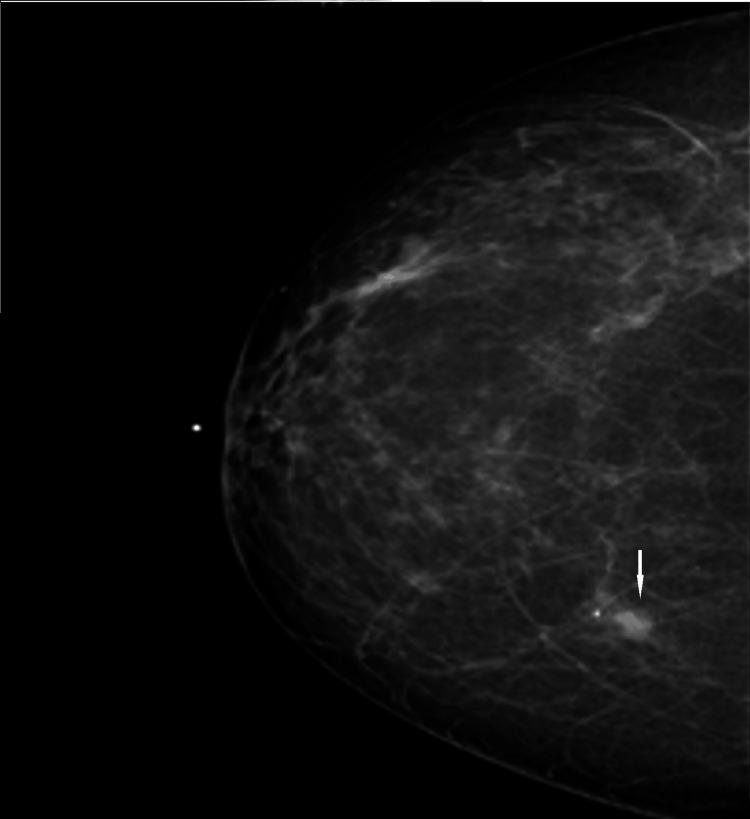

We describe a case of pathology-proven invasive lobular breast cancer (ILC) arising in a scar over 15 years after lumpectomy for previous invasive ductal carcinoma (IDC). The tumor was detected on screening mammography as a new focal asymmetry at the scar site and confirmed at diagnostic mammography. Ultrasound demonstrated an irregular, shadowing, hypoechoic mass at the scar site. Ultrasound-guided biopsy revealed poorly differentiated invasive lobular carcinoma. MRI and CT showed an irregular mass with pectoralis muscle invasion. Multimodality imaging findings are described. This is the first case to our knowledge reporting multimodality imaging findings of a breast cancer developing at the site of a surgical scar that is histologically different from the originally resected cancer.

我们描述了一例经病理证实的浸润性小叶乳腺癌(ILC)病例,该病例发生于先前因浸润性导管癌(IDC)行肿块切除术后15年以上的瘢痕处。肿瘤在筛查乳腺X线摄影中被检测为瘢痕部位新出现的局灶性不对称,并在诊断性乳腺X线摄影中得到证实。超声显示瘢痕部位有一个不规则、有阴影、低回声肿块。超声引导下活检显示为低分化浸润性小叶癌。MRI和CT显示有一个不规则肿块,侵犯胸大肌。描述了多模态成像结果。据我们所知,这是首例报告手术瘢痕部位发生的组织学上与最初切除的癌症不同的乳腺癌的多模态成像结果的病例。